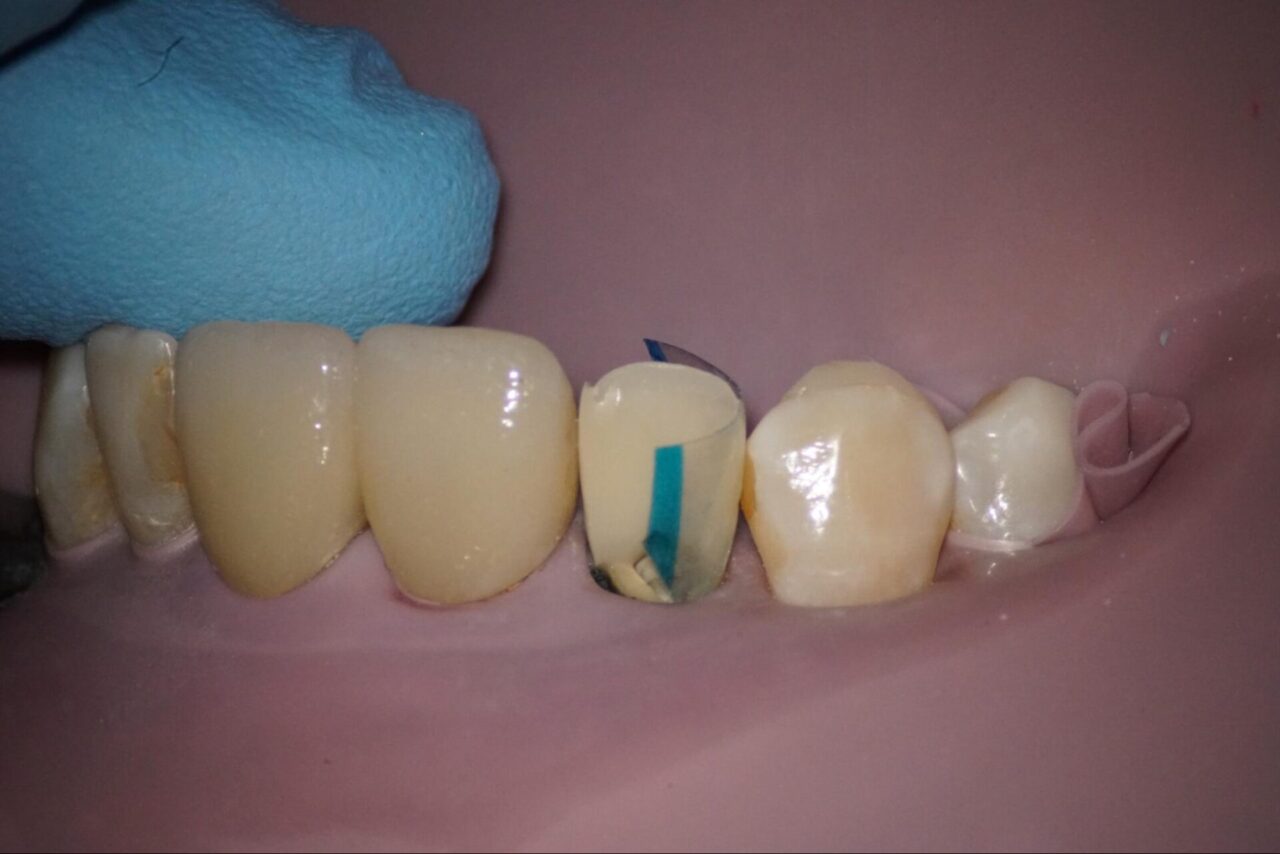

その後にクラックラインの接着を確実に行うため酸化アルミナによるブラスト処理を行います。

この症例では、光硬化型のボンディング材を用いたので根管内に光が届くように特殊な器具を用いてボンディング材の硬化をさせます。

特に前歯なので、歯がない状態で終了する事はできません。コンポジットレジンにて歯冠形態を作り、今日は終了です。

歯と歯茎の間に入れた仕掛けを外して今日は終了です。

次回問題がなければ、裏側から根管内にアクセスしてファイバーコアにて築造を行います。